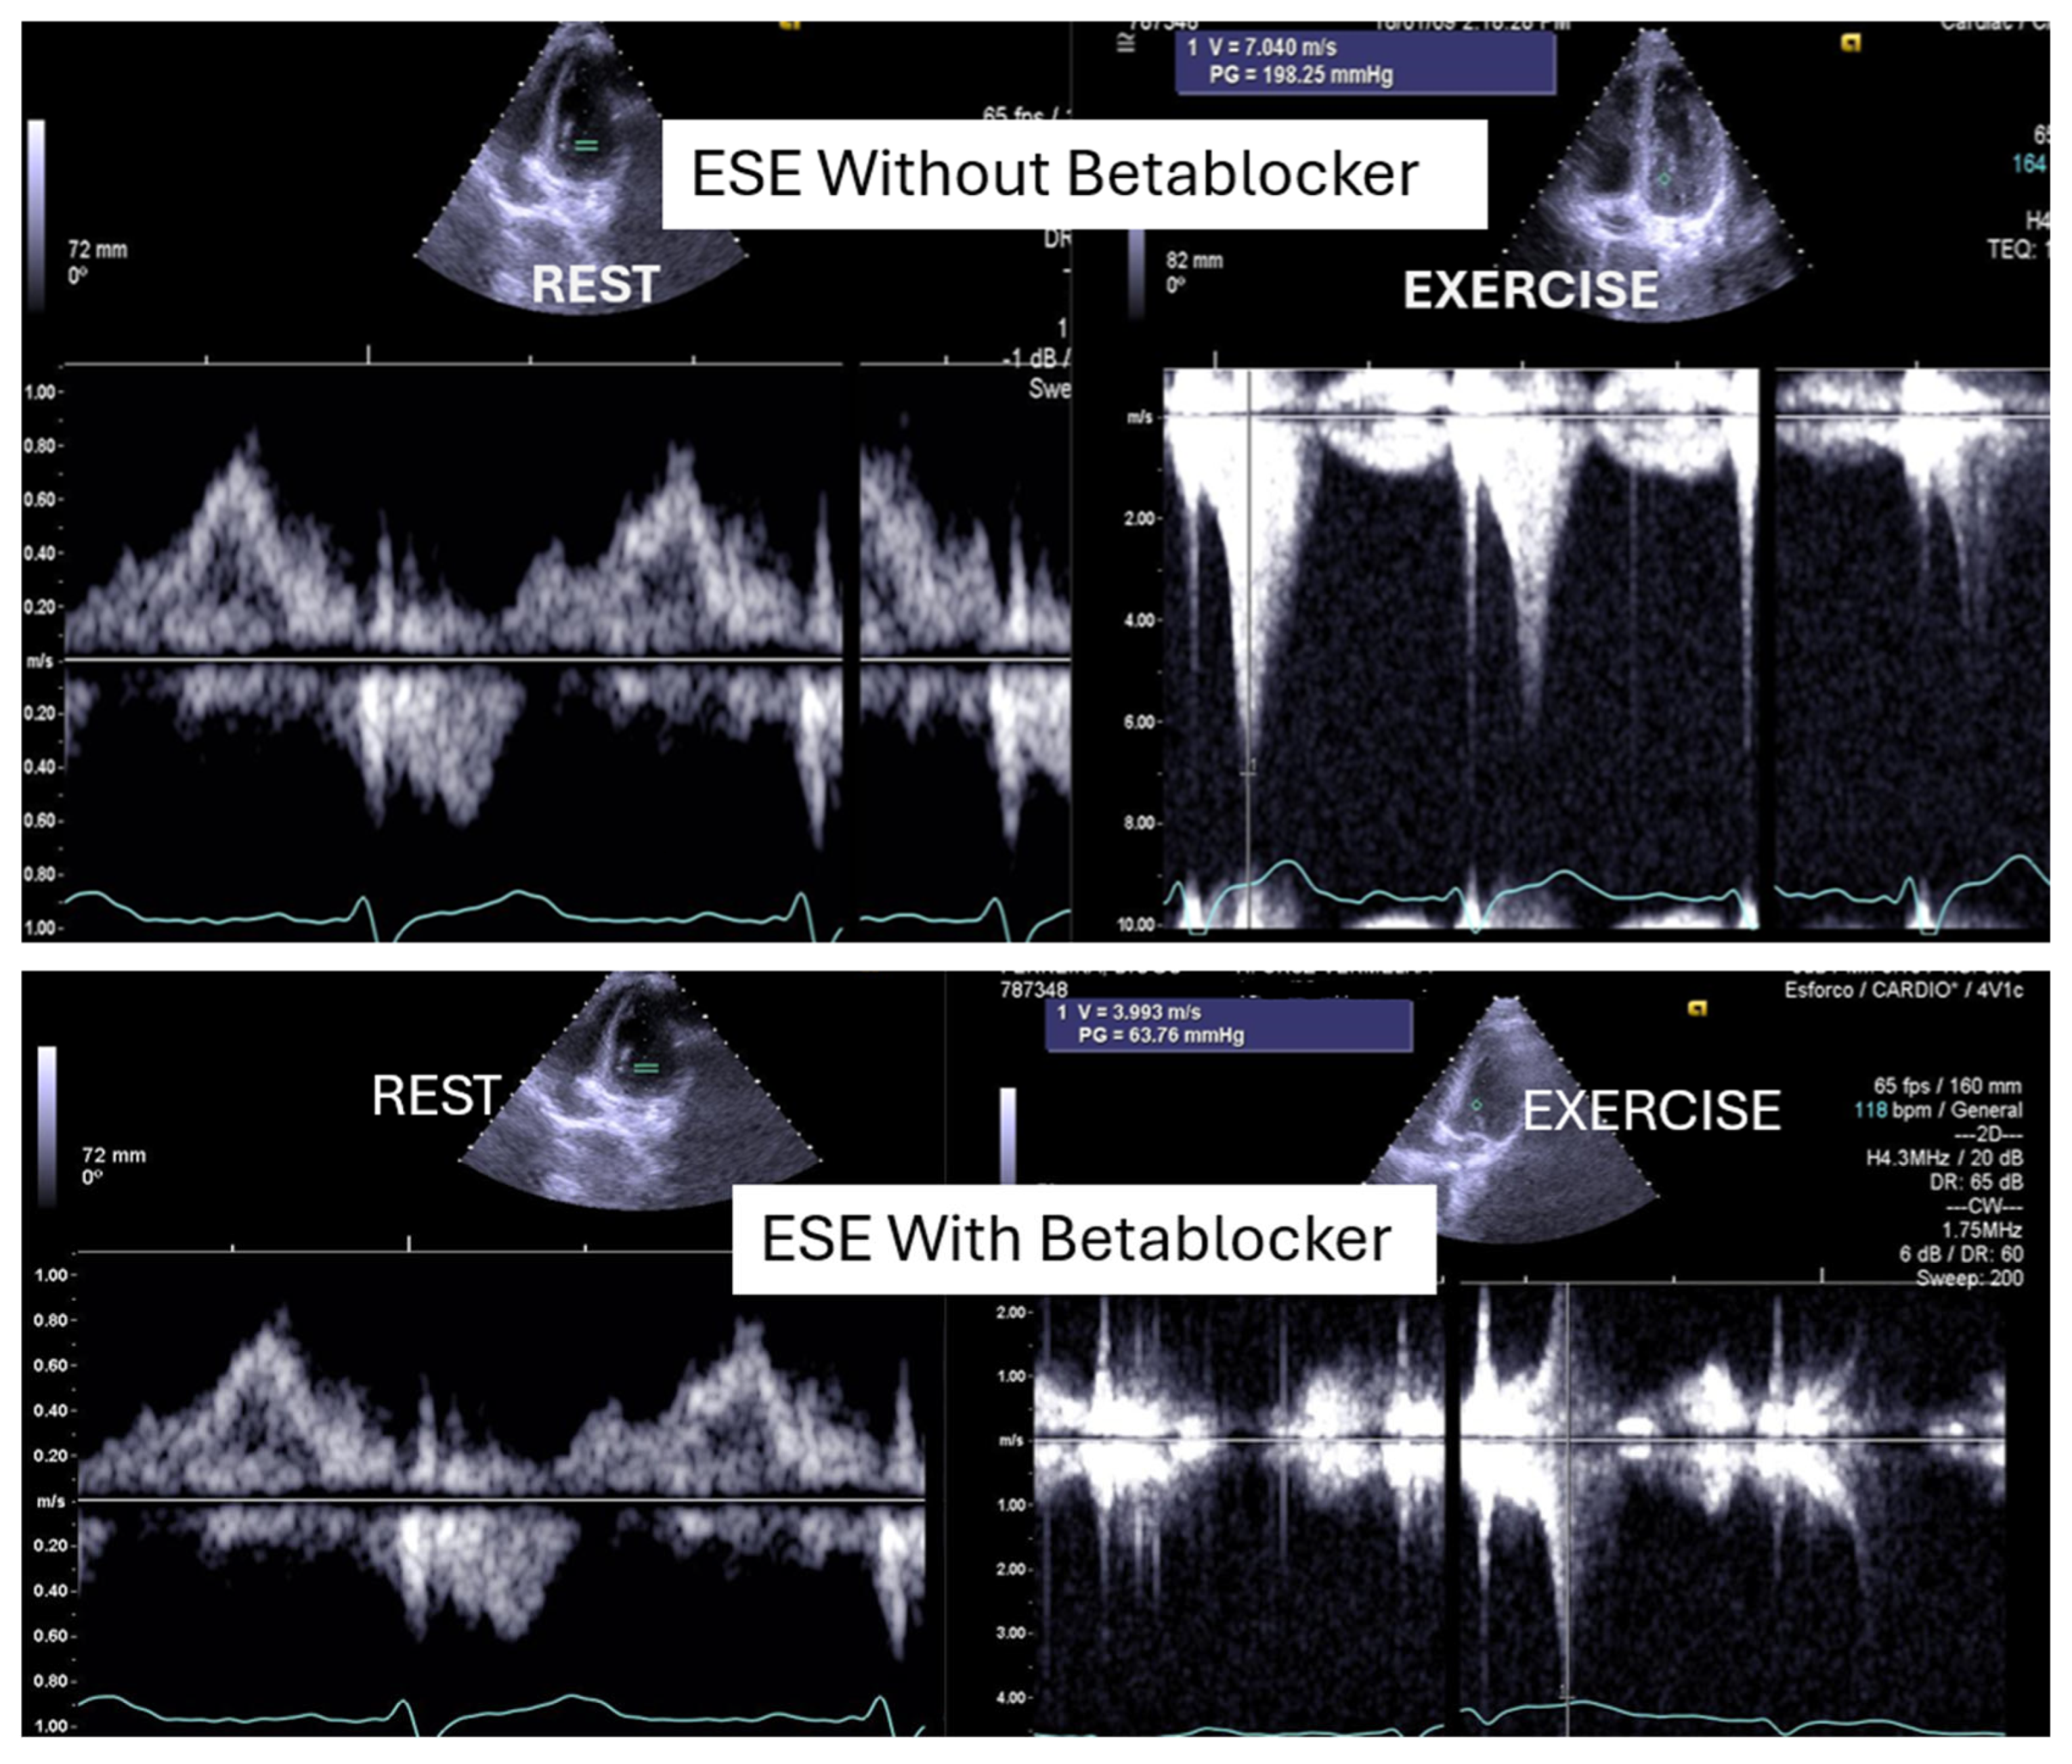

Of the 66 children enrolled in the study, 15 (23%) were female. The mean age was 14,6, 1,7 years old (11 to 17). On the resting echocardiogram, all the exams were considered normal with and without beta blockers. No wall motion abnormalities were detected in any of the exams, with or without beta blockers. IVPG (Figure 1) at peak exercise on the first assessment was 105 ± 38 mmHg, with mitral valve SAM in 28 children (Figure 2) in the complete group and 58 + 32 mmHg in only 29 children treated with beta-blockers, P< 0.0001.

Figure 1. This figure shows an intraventricular gradient during exercise in a child experiencing exercise-related chest pain and syncope, accompanied by elevated troponin levels (top). A significant reduction in the gradient is observed under beta-blocker therapy (bottom).

In our study, beta-blocker therapy was associated with a reduction in heart rate, exercise-induced ST-segment alterations, systolic blood pressure, and consequently, peak heart rate–systolic blood pressure product (HR×SBP). The incidence of intraventricular gradients (IVG) (Figure 1) and systolic anterior motion (SAM) of the mitral valve (Figure 2) during exertion also decreased significantly. These hemodynamic improvements were accompanied by a notable reduction in symptoms during exercise testing and follow-up (Figure 3 and Figure 4).

Figure 8. – This composite image shows a child from the study during three exercise stress echocardiograms (ESE): the first with significant IVPG, the second with IVPG despite taking 2.5 mg of bisoprolol, and the third without significant IVPG, taking 5mg of bisoprolol.